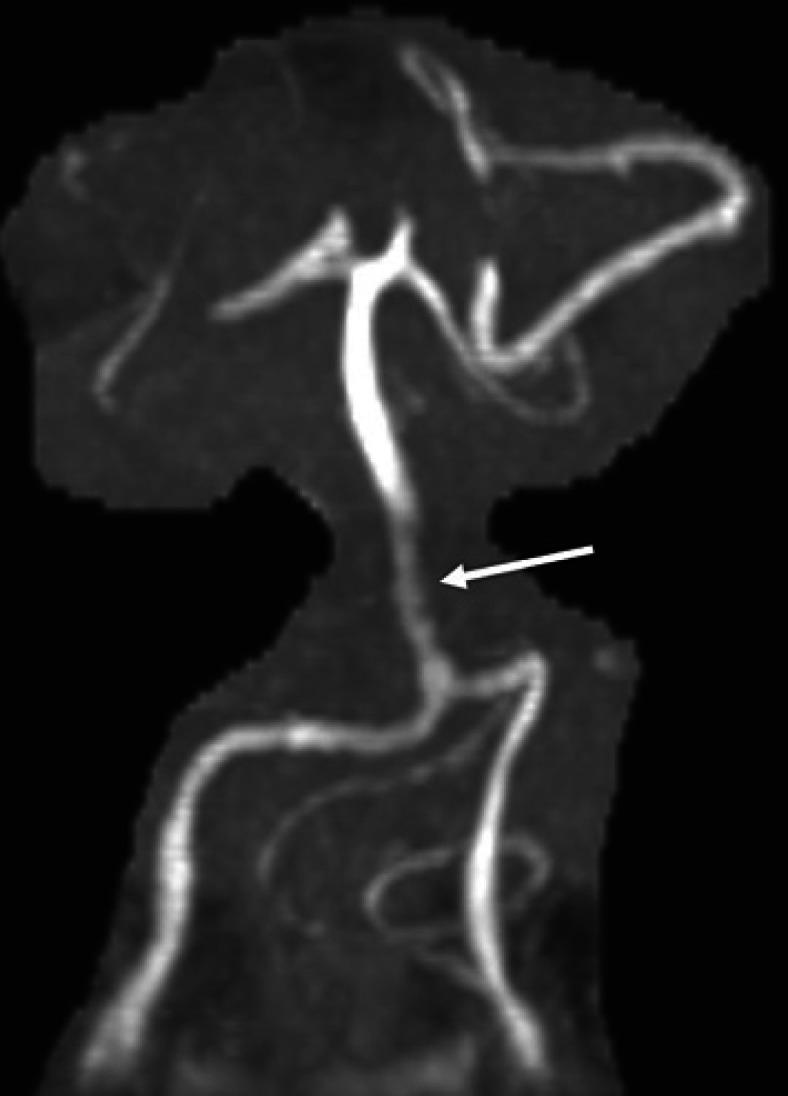

Differentiating GCA from its many mimickers remains a challenge in the daily clinical practice, especially in patients presenting with unspecific manifestations. We present the case of an 82-year-old woman who presented with a 3-week history of left eye vision loss secondary to bilateral edema and hemorrhage of the optic discs. Despite negative bilateral temporal artery biopsies, the elevation of the inflammatory markers and brain MRA findings suggestive of temporal arteritis as well as stenosis of the basilar artery led us to initiate treatment with high-dose steroids. Inflammatory markers remained elevated despite high-dose steroids which prompted additional work leading to a diagnosis of varicella-zoster encephalitis. Steroid treatment was quickly tapered off and treatment with acyclovir resulted in the normalization of the acute phase reactants. The persistence of elevated inflammatory markers despite high-dose steroids should prompt additional work up for the search of an alternative diagnosis of GCA mimickers.

在日常临床实践中,将巨细胞动脉炎(GCA)与众多相似疾病区分开来仍然是一项挑战,尤其是对于表现为非特异性症状的患者。我们报告了一例82岁女性患者,她因双侧视盘水肿和出血导致左眼视力丧失,病程3周。尽管双侧颞动脉活检结果为阴性,但炎症标志物升高、脑部磁共振血管造影(MRA)结果提示颞动脉炎以及基底动脉狭窄,促使我们开始使用大剂量类固醇进行治疗。尽管使用了大剂量类固醇,炎症标志物仍持续升高,这促使我们进一步检查,最终诊断为水痘-带状疱疹脑炎。类固醇治疗迅速减量,阿昔洛韦治疗使急性期反应物恢复正常。尽管使用了大剂量类固醇,炎症标志物仍持续升高,这应促使我们进一步检查,以寻找GCA相似疾病的替代诊断。